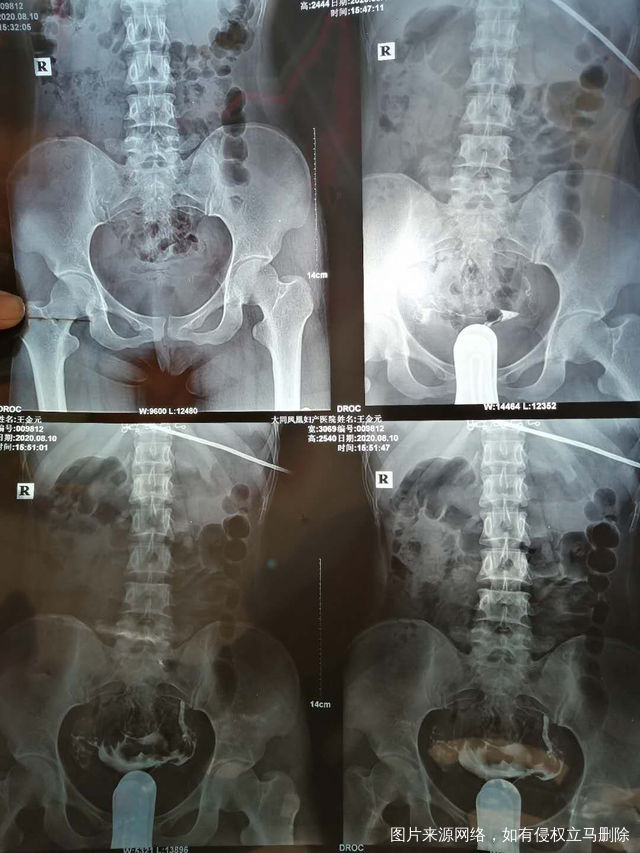

照影的结果是一边通而不畅一边显影并上举请问医